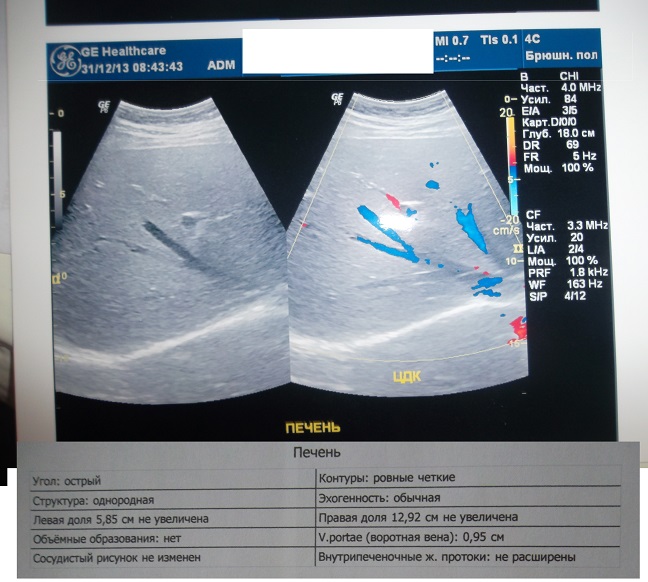

Поехали сдали анализы в кишиневе(была надежда что ошибка) и сходили на узи В кишиневе были на консультации терапевта- не гепатолога.